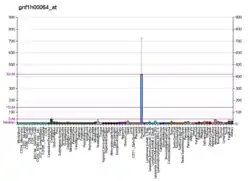

This gene is one of the fifteen kallikrein subfamily members located in a cluster on chromosome 19. In some tissues its expression is hormonally regulated. The expression pattern of a similar mouse protein in murine developing teeth supports a role for the protein in the degradation of enamel proteins.[9] Alternate splice variants for this gene have been described, but their biological validity has not been determined.[10]